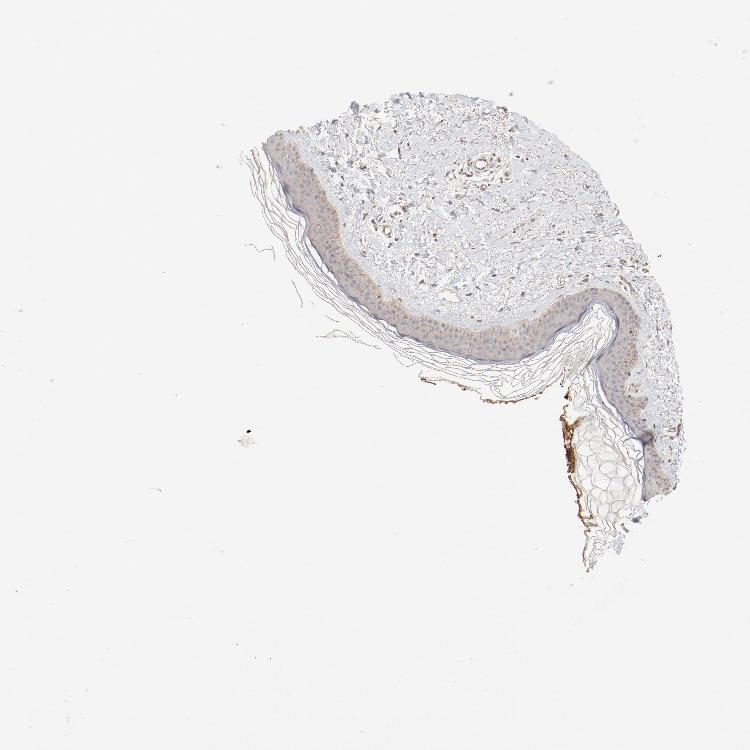

SKIN 1 - Antibody stainingi

Antibody staining in the annotated cell types in the current human tissue is reported as not detected, low, medium, or high, based on conventional immunohistochemistry profiling in selected tissues. This score is based on the combination of the staining intensity and fraction of stained cells.

Each image is clickable and will lead to virtual microscopy that enables deeper exploration of all samples and also displays staining intensity scores, fraction scores and subcellular localization as well as patient and tissue information for each sample.

Antibody HPA003539Antibody CAB018374

Langerhans MediumLow

Fibroblasts MediumMedium

Keratinocytes Not detectedLow

Melanocytes LowLow